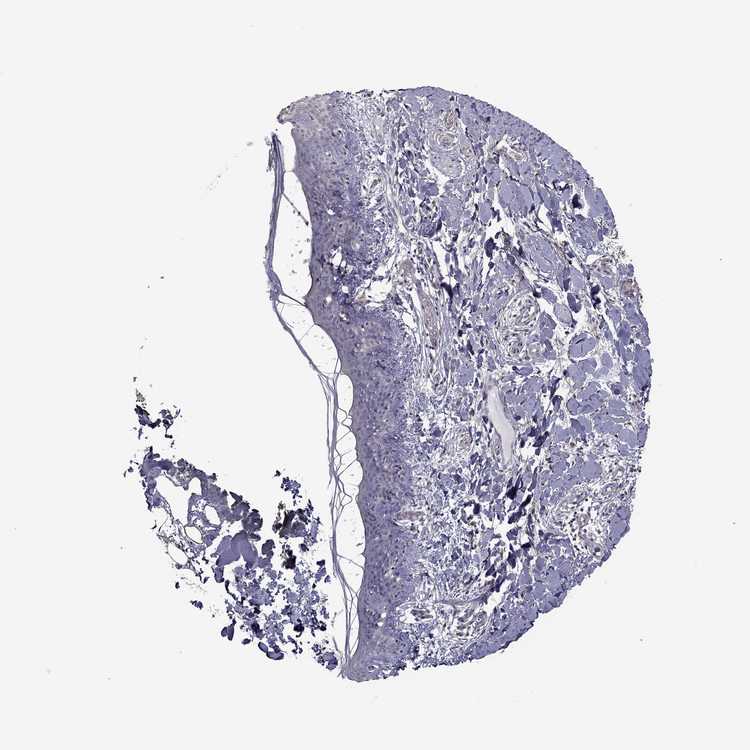

SKIN 1 - Antibody stainingi

Antibody staining in the annotated cell types in the current human tissue is reported as not detected, low, medium, or high, based on conventional immunohistochemistry profiling in selected tissues. This score is based on the combination of the staining intensity and fraction of stained cells.

Each image is clickable and will lead to virtual microscopy that enables deeper exploration of all samples and also displays staining intensity scores, fraction scores and subcellular localization as well as patient and tissue information for each sample.

Antibody HPA022974

Langerhans Not detected

Fibroblasts Not detected

Keratinocytes Not detected

Melanocytes Not detected